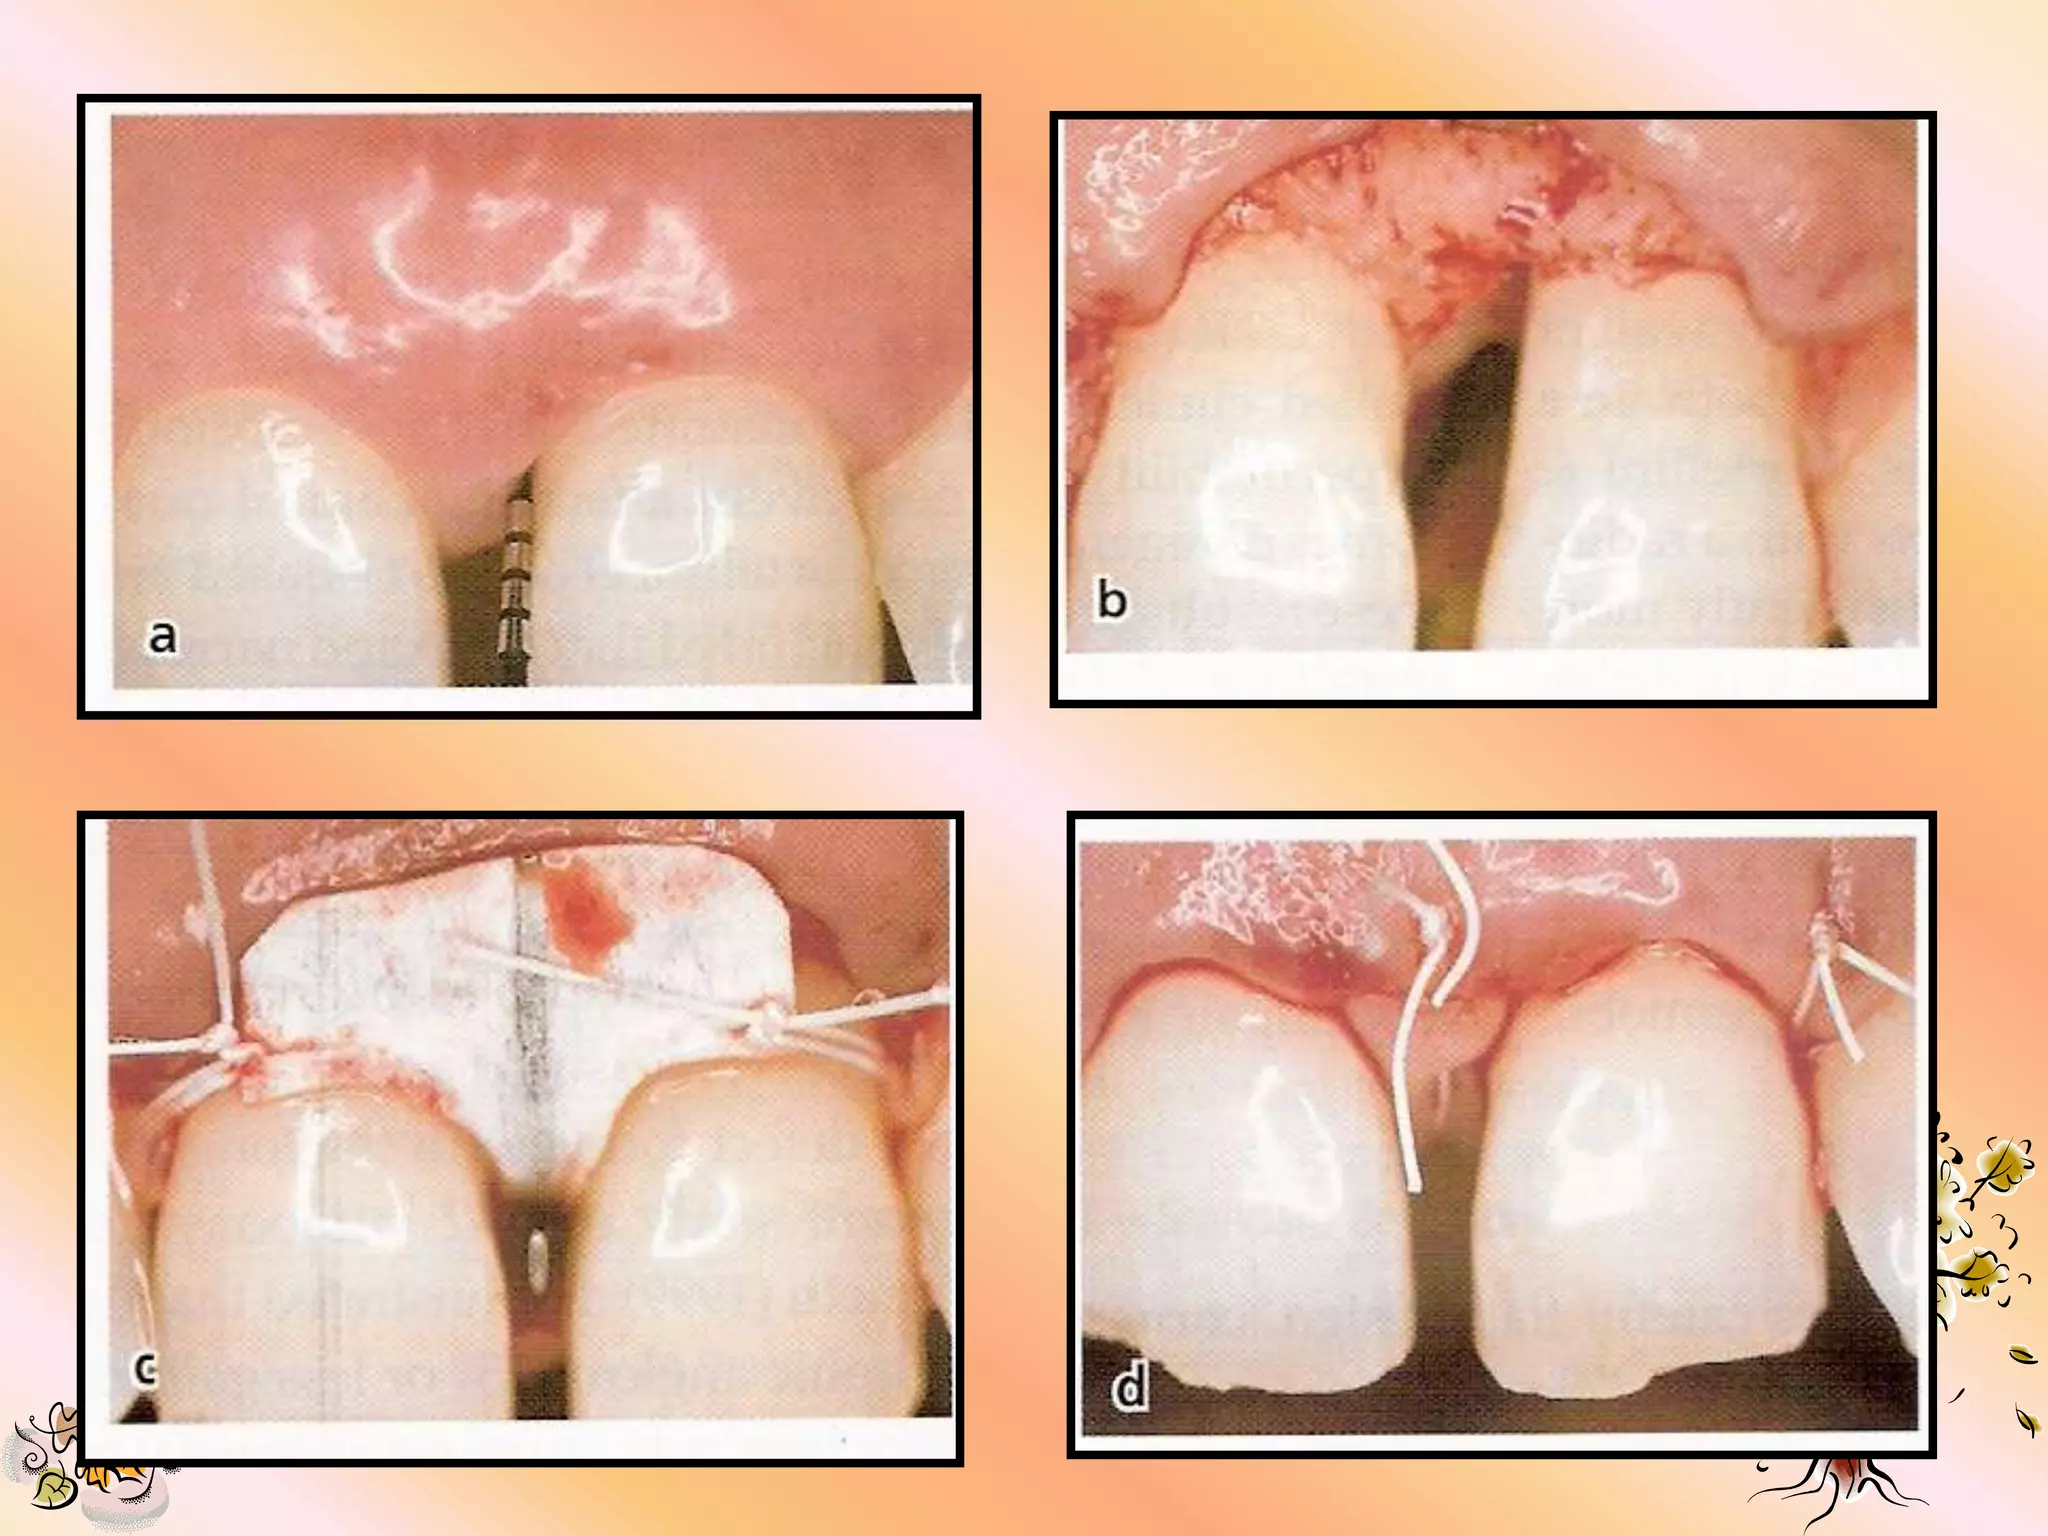

1.   Intra sulcular incisions are made in

preparation for a full mucoperiosteal flap.

2. All residual pocket epithelium is removed

after flap reflection to permit integration

b/w the e-PTFE & flap connective tissue.

3. Incision should extend 1-2 teeth mesial &/

or distal of the area being treated to permit

adequate visualization.

4. Vertical incision should be placed mesially

where necessary.

SUTURE MATERIAL

1.   Gore-Tex suture (provided with material) is

recommended for placing the material & flap

closure.

2. Silk or monofilament suture may be used in

areas away from the material.

3. Bioabsorbable sutures are not recommended.

SUTURING TECHNIQUES

1.   Sling suture are used to approximate

material over the defect without engaging

the flap or tissue.

2. The material must fit tightly against the

tooth surface at all points to prevent

epithelial proliferation b/w tooth & material

& to help in stabilizing the wound.

3. The flap margin should ideally be 2 to 3 mm

coronal to the material.

4. Tight flap apposition is desired to avoid

premature flap opening & material exposure.